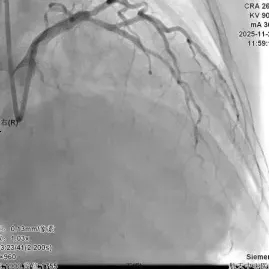

入院后第4天苏工介入团队为患者行冠脉造影术,提示前降支在发出第一对角支后呈现100%闭塞状态,第一对角支近段存在长节段病变,最大狭窄程度达90%。苏工副主任领衔的冠脉介入团队经多维度研讨,尝试开通前降支闭塞病变,开通后对介入术式进行评估。 经过多次反复尝试,导丝通过前降支闭塞病变,考虑第一对角支近段病变重,为分叉病变,术式采用DK-CRUSH,整个手术过程历时2小时,术后TIMI血流3级。

PCI术后